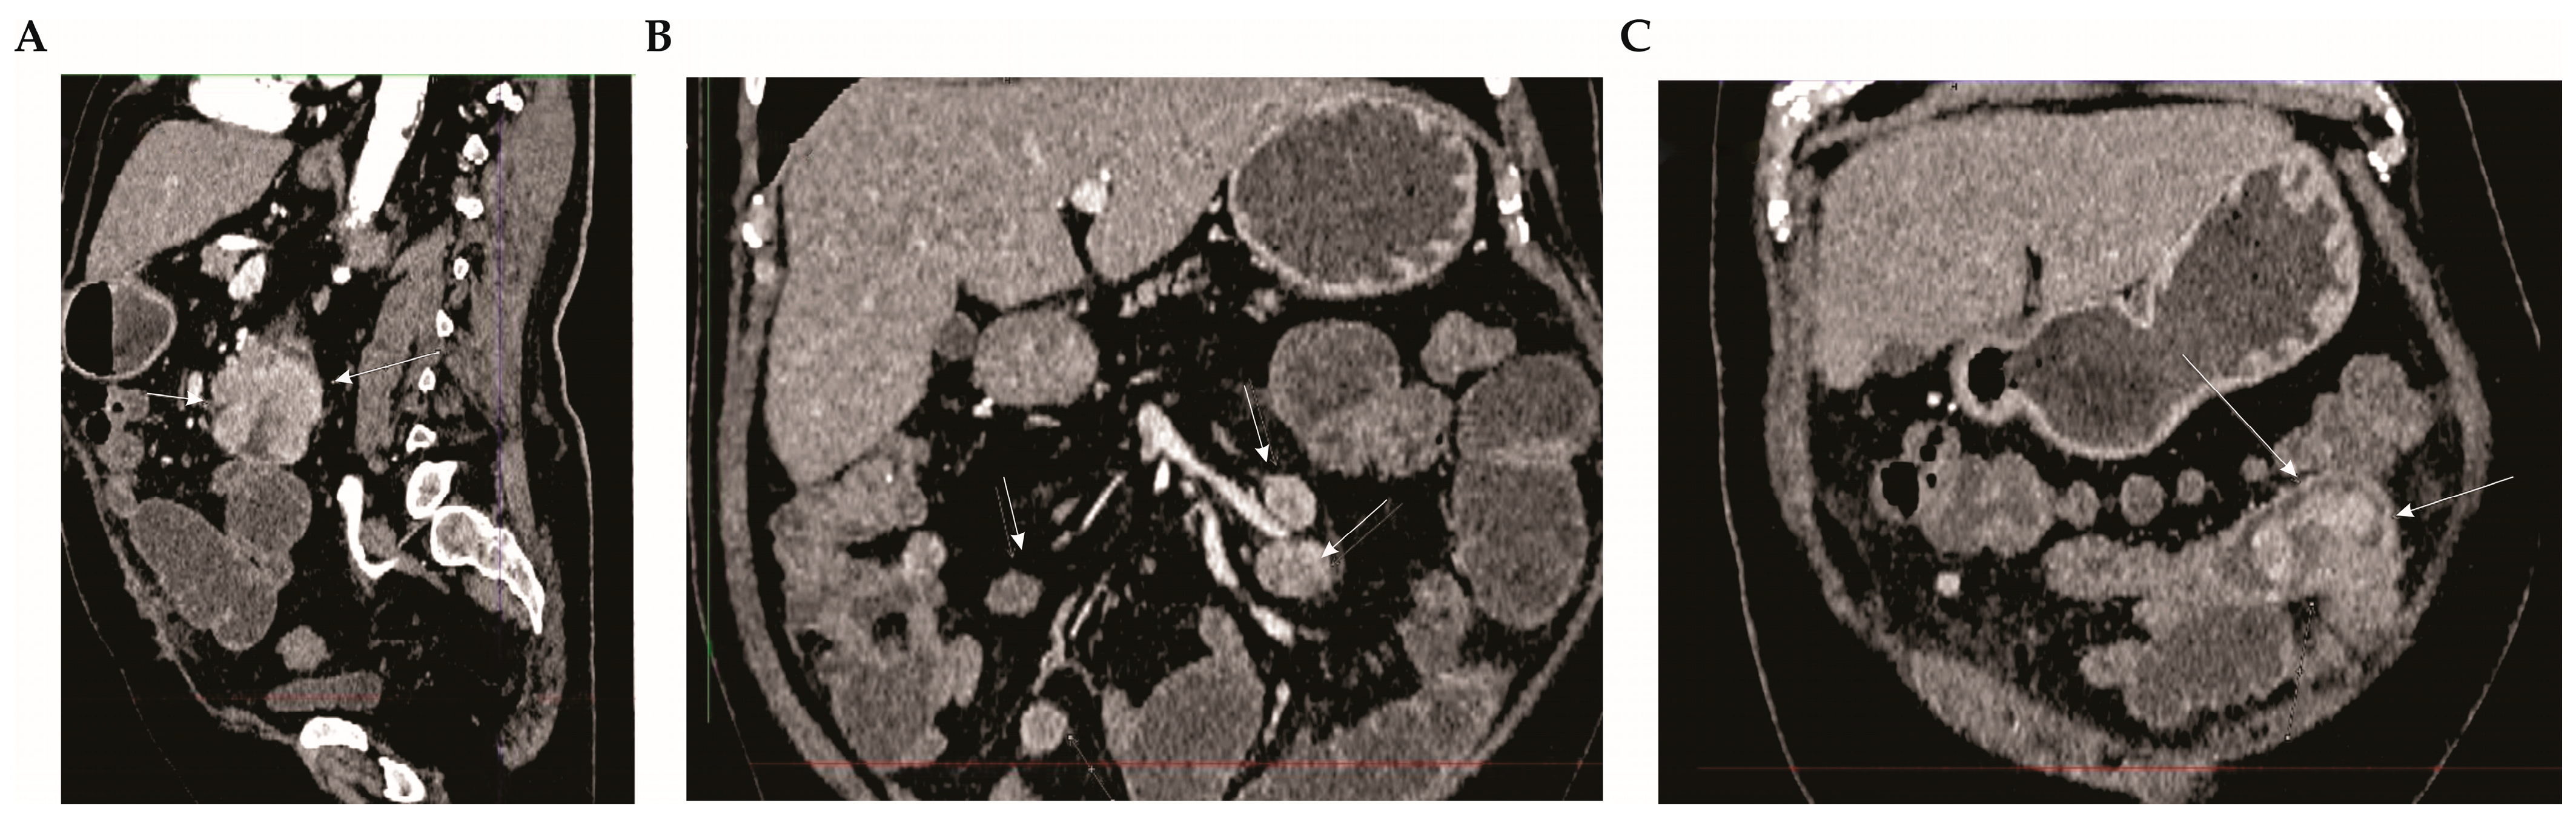

2.2. Diagnostic Assessment

2.3. Therapeutic Intervention